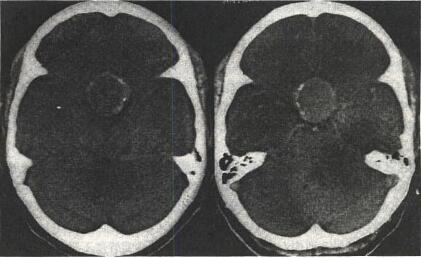

儿童颅咽管瘤是儿童最常见的颅内先天性肿瘤。据了解,在我国人群中的颅咽管瘤发病率占全部颅内肿瘤的4.7-6.5%。其中,70%为15岁以下的儿童。由于儿童颅咽管瘤首发症状表现为视力下降,极易被误诊,因此家长一定不能掉以轻心。

有父母带孩子来我科室就诊,讲诉孩子视力下降,头晕,但在眼科检查后发现并不是眼睛的问题,于是来神经外科检查,CT检查后发现:孩子所患的是颅咽管肿瘤,这是父母没有想到的,也是此类肿瘤容易被误诊或耽误的原因。” 第四军医大学第一附属医院西京医院神经外科教授贺晓生主任说,颅咽管瘤是一种良性先天性肿瘤,但其生长常累及下丘脑重要结构,所以需要彻底切除,以免影响患者的生长发育。但遗憾的是,由于家长或一些非专科医务人员缺乏相关知识,使患儿就诊太迟或不能得到有效治疗。如果当患儿视力严重损害后,即使开颅手术切除肿瘤,视力的损害也不能完全恢复,甚至失明。

选择正规大医院就诊